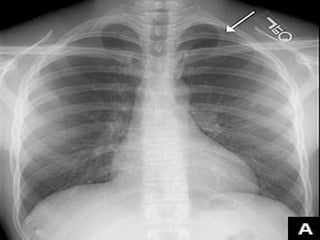

Définition du caractère complet :

 PNO complet: décollement de tout le poumon, quelle

que soit l’importance de l’épanchement.

 PNO incomplet: décollement partiel du poumon

(sommet++).

Appréciation de la taille du pneumothorax :

   mesure de la distance séparant la ligne

bordante du sommet :

< ou = 3 cm : Faible abondance.

> 3 cm : moyenne ou forte abondance.

   L’idéal : volume du pneumothorax exprimé en

%.

V = 1 – (B3/A3)*100.